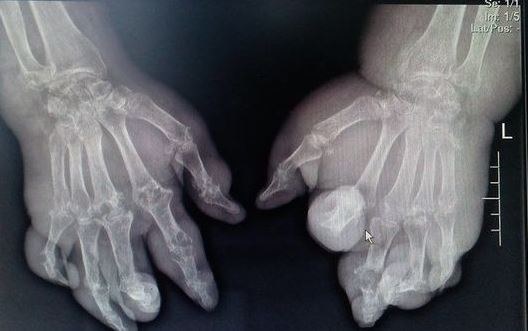

痛風發作一旦進入慢性階段,隨著炎症問題的加劇,尿酸在各個部位的皮下組織積累成為尿酸鹽結晶,結晶體像一個個瘤體一樣從皮下組織鼓起來,進而就形成了痛風石。

X光下痛風石 圖源:網路

首次痛風發作,再到慢性症狀的形成,或者是出現痛風石,中間的時間差異很大。有的患者在兩三年即可形成痛風石,有些患者則會發作幾十年後形成痛風石。整體來看,尿酸水平越高,痛風發作的頻率越高,痛風石形成的可能性就越大。

至於痛風石是否會消失,要看痛風石出現的部位,痛風石的大小以及痛風石的性狀。

關節部位較小的痛風石,透過積極的治療和控制尿酸,在尿酸長期保持在合理的狀態下,痛風石有可能消失。此外,痛風石如果小於1.5釐米,形成時間較短,痛風石沒有硬化,在積極治療的情況下,都有可能消失。

但是,如果痛風石出現非關節區域的皮下組織,而且痛風石的直徑較大,則不太容易消失。此外,痛風石形成時間長了,出現硬化現象後,也不容易自行消失。